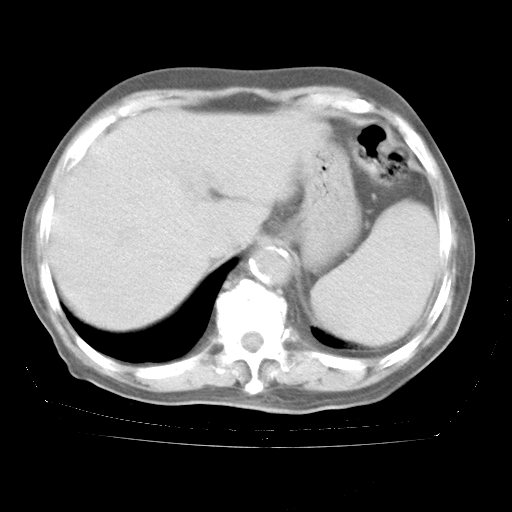

今天部分检查

轻微咳嗽,无痰,(体温正常时)R20次/分,P75次/分,双肺底、腋下可闻及少量捻发音。下肢轻度浮肿。

血常规:白细胞9.11×109/L,N0.92,L5.64,血小板39.2×109/L,HB148g/L,ESR2mm/H。

尿常规:潜血+

血生化:总蛋白69.71g/L,白蛋白38.40g/L,球蛋白31.31g/L,CRP27.9mg/L,尿素氮11.98mmol/L,肌酐106μmol/L,乳酸脱氢酶1099 U/L,肌酸激酶108U/L,CK-MB 61U/L。

腹部B超:胆囊壁增厚,肝、胆、胰、脾、肾无异常,肠系膜淋巴结、腹膜后淋巴结无增大。